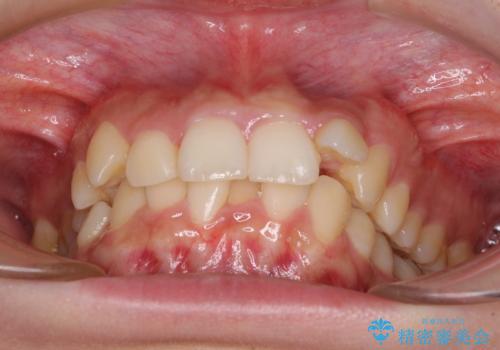

下顎前歯が隠れて突出した口元 ワイヤー装置での抜歯矯正

- 前歯のデコボコと口元の突出感を気にして来院された患者様です。

下顎骨の左右差や、上顎骨の前方位などが認められたため、上下左右の第1小臼歯4本を抜歯し、ワイヤー装置にて矯正治療を行うこととしました。

骨格的な左右差がありましたが、何とか当初予定していた期間で、左右対称の咬み合わせに仕上げることができました。